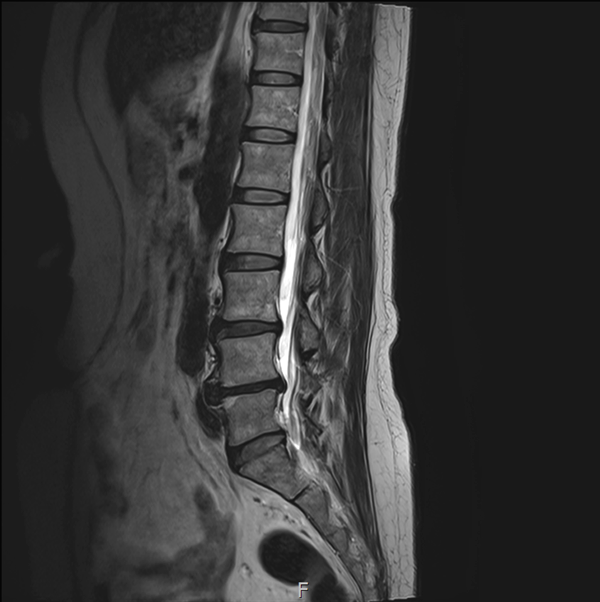

MRI (자기공명영상)

허리디스크 진단의 정석!

디스크 위치, 신경압박, 퇴행 정도 꼼꼼히 파악

척추관 협착증 같은 동반 질환도 확인 가능